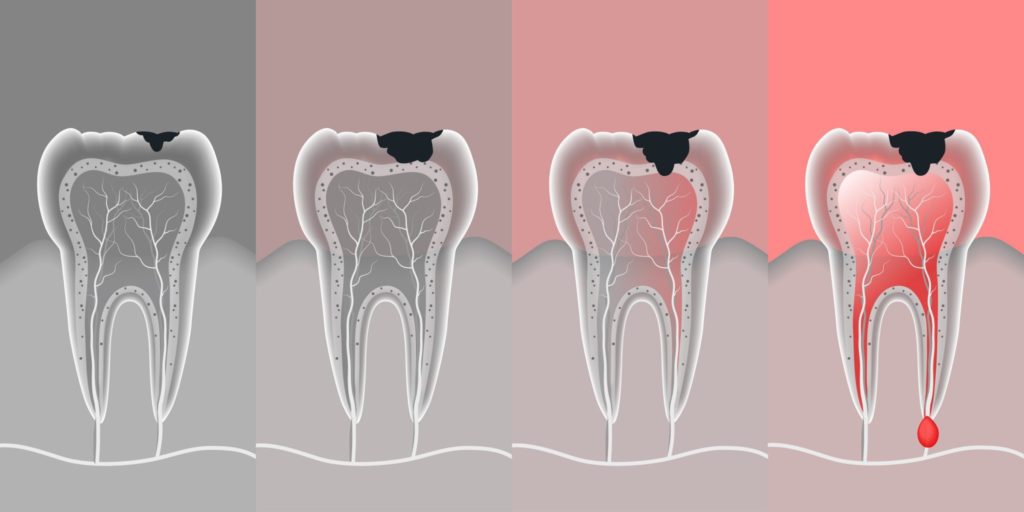

Stages Of Dental Decay And Periodontal Disease | High Dosage

www.highdosage.com

www.highdosage.com

dental decay disease caries stages teeth

Digital Image Of Stages Of Tooth Decay | Dentist Denver & Lone Tree

www.metrodentalcare.com

www.metrodentalcare.com

tooth decay dental cavity stages root abscessed fillings why enamel symptoms cavities pain types teeth canal pulp filling if does

Tooth dental decay abscess stages caries dentagama phoenix pain pulp infection teeth bone like spread look mouth periodontal severe enamel. Symptoms and treatments of dental caries. Stages of dental decay and periodontal disease